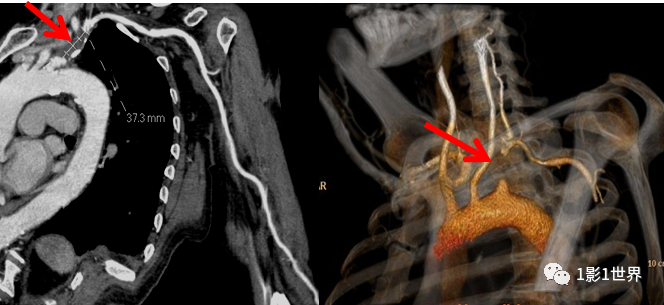

中年男性,因经常性头晕伴左上肢无力、肢体发凉就诊。查体:双上肢脉压差较大,收缩压左侧较右侧低40mmHg,左侧桡动脉搏动较弱、皮温略低。临床怀疑锁骨下盗血综合征,首先行CTA检查,发现病变,后经DSA血管造影证实,最后诊断:左侧锁骨下动脉近端狭窄(>75%)。

锁骨下动脉盗血综合征,是指一侧锁骨下动脉或无名动脉在椎动脉近段狭窄或闭塞,机体代偿的结果,椎动脉血流逆流入锁骨下动脉,供应上肢,却引起椎-基底动脉供血不足的症状。

常见病因是动脉粥样硬化,其次为特异性和非特异性动脉炎。

临床上男性较多,左侧多发,常在患侧上肢活动时出现发作性头晕、视物模糊及脑干、枕叶、小脑供血不足表现,患侧上肢感觉异常、无力、皮肤苍白、肌肉疼痛等。

本例,介入科行“左侧锁骨下动脉支架植入术”,术中先行狭窄处球囊扩张,造影显示扩张满意后置入支架。术后,患者立即感到左上肢温暖,第3天出院。